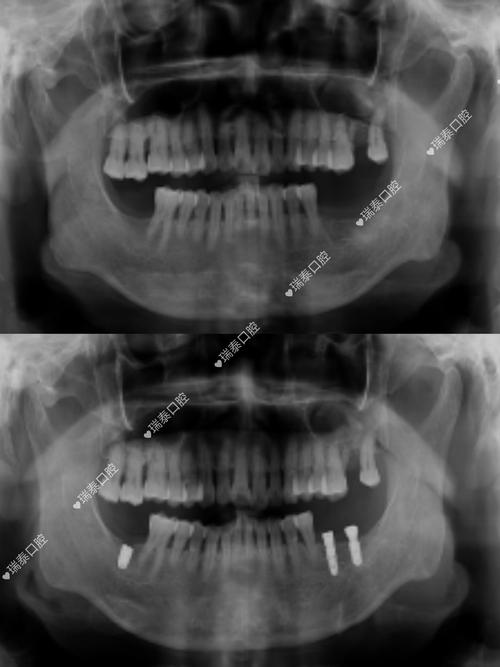

- 种植体位置: 确认种植体是否放置在理想位置。

- 骨结合情况: 观察种植体与周围骨组织是否良好结合(骨整合)。

- 并发症排查: 检查是否有感染、神经损伤、上颌窦穿孔等问题。